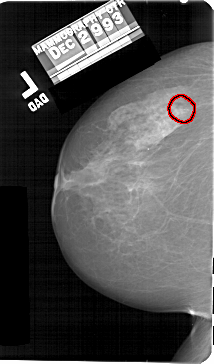

A_1565_1.LEFT_MLO

LEFT_MLO LINES 5491 PIXELS_PER_LINE 3511 BITS_PER_PIXEL 12 RESOLUTION 43.5 OVERLAY

FILE: A_1565_1.LEFT_MLO.OVERLAY

TOTAL_ABNORMALITIES 1

ABNORMALITY 1

LESION_TYPE CALCIFICATION TYPE AMORPHOUS DISTRIBUTION CLUSTERED

ASSESSMENT 4

SUBTLETY 3

PATHOLOGY BENIGN

TOTAL_OUTLINES 1

BOUNDARY